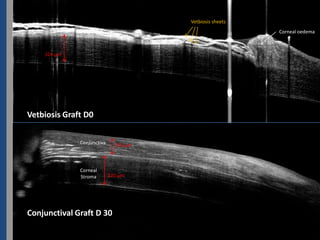

Vetbiosis sheets

Corneal oedema

324 µm

Vetbiosis Graft D0

Conjunctiva     150 µm

Corneal

Stroma        320 µm

Conjunctival Graft D 30sans vetbiosi (légender les images